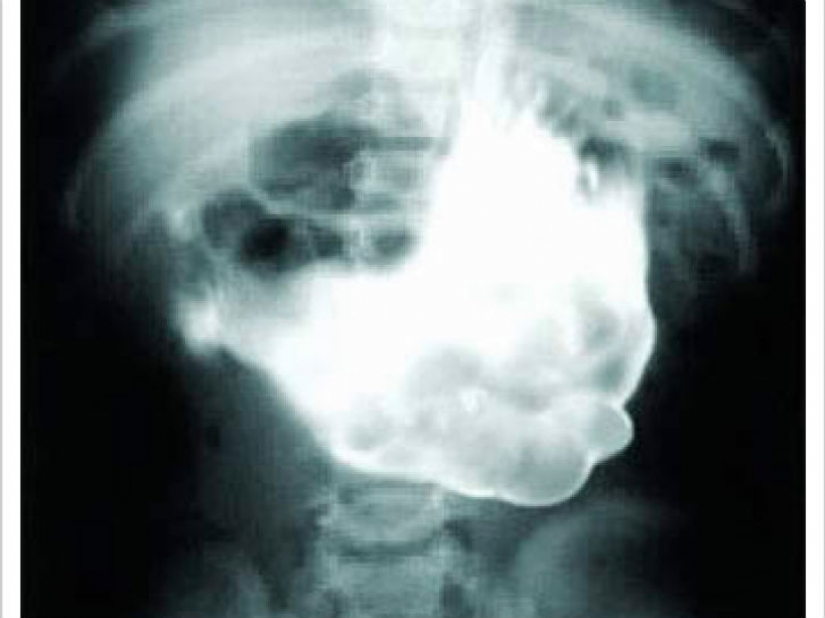

Nos advirtió que, de no mirar si simplemente se sentó a almorzar. Uno de 18 años de edad, niña fue retirado del estómago hairball con 4,5 kg.